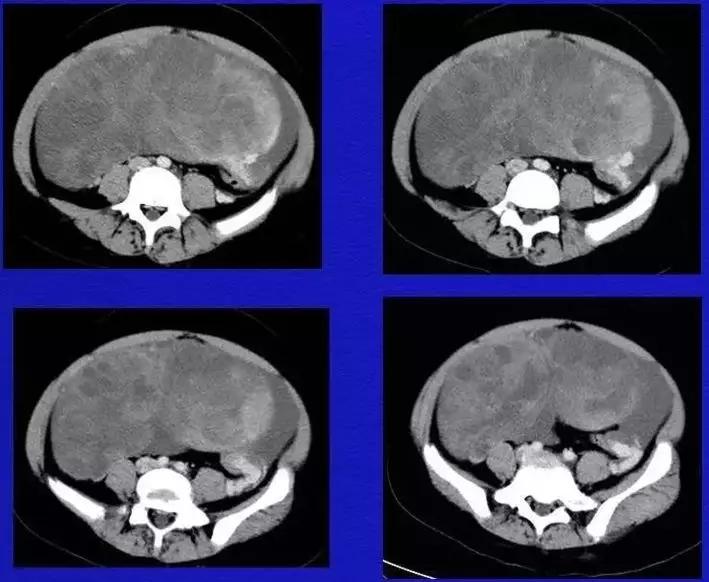

病理:子宫肌瘤粘液样变性

病例4 女,32岁,以“月经量增多伴经期延长半年。”

缘于患者入院前半年无明显诱因出现月经量增多,卫生巾由原来3包余增至5包不等,伴血块,经期由原来7天延长至10-15天不等,无痛经,无月经周期改变,无阴道异常排液,无畏冷、发热,无头晕、乏力等不适,未重视,未诊治。期间症状持续。2月前就诊我院,查彩超示:“子宫体大小约5.7*5.3*4.6cm,内膜厚约0.6cm,回声不均,左卵巢旁探及大小约4.2*3.5cm低回声区。”建议治疗,患者及家属表示考虑。期间症状持续,今就诊我科门诊,要求住院手术治疗,无腹痛等不适,门诊拟“卵巢囊肿”收住入院。既往史:2007年剖宫产一次,术顺。月经史:15 7/25 lmp2018.05.14,量中,无痛经。婚育史:已婚,1-0-3-1,末孕2007年剖宫产娩一男婴,儿子及丈夫体健。个人史、家族史均无特殊。

CA125 335.5(U/mL);2018-05-30 彩超:子宫宫体大小约5.6㎝×6.3㎝×4.9㎝,形态正常,宫壁回声欠均,内膜厚约1.8cm,回声不均。CDFI:子宫内未见明显异常彩色血流信号。左附件区探及一混合回声团块,大小约9.8㎝×7.9㎝,CDFI:其实性部分可见少许彩色血流信号。右附件区未见明显包块回声。